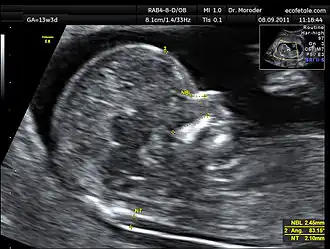

Measurements of fetal nuchal translucency, nasal bone and facial angle according to the standards of the Fetal Medicine Foundation

A nuchal scan or nuchal translucency (NT) scan/procedure is a sonographic prenatal screening scan (ultrasound) to detect chromosomal abnormalities in a fetus, though altered extracellular matrix composition and limited lymphatic drainage can also be detected.[1]

Procedure

Nuchal scan (NT procedure) is performed between 11 and 14 weeks of gestation, because the accuracy is best in this period. The scan is obtained with the fetus in sagittal section and a neutral position of the fetal head (neither hyperflexed nor extended, either of which can influence the nuchal translucency thickness). The fetal image is enlarged to fill 75% of the screen, and the maximum thickness is measured, from leading edge to leading edge. It is important to distinguish the nuchal lucency from the underlying amniotic membrane.[9]

Normal thickness depends on the crown-rump length (CRL) of the fetus. Among those fetuses whose nuchal translucency exceeds the normal values, there is a relatively high risk of significant abnormality.